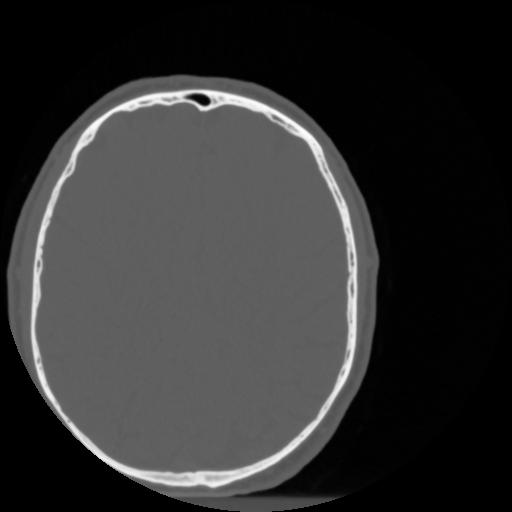

4 CEREBRO,,Vol,0.5,CEREBRO,,